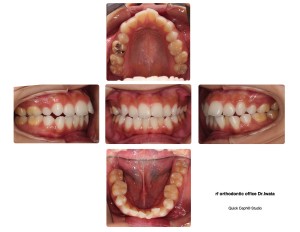

インビザライン矯正を始める前からの比較画像を載せます。

【スタート前】

↓

【スタートして4ヶ月後】

【今回の診察】

下の歯はガタガタが解消されていますね。

さらに右上の親知らずを抜歯したことで、その手前の歯と歯の間に5ミリほど隙間が出来ました!(横向きの写真を見ると分かり易いです)

この隙間はのちのステップで重要なんだそうです!隙間が出来たことは順調の証!!